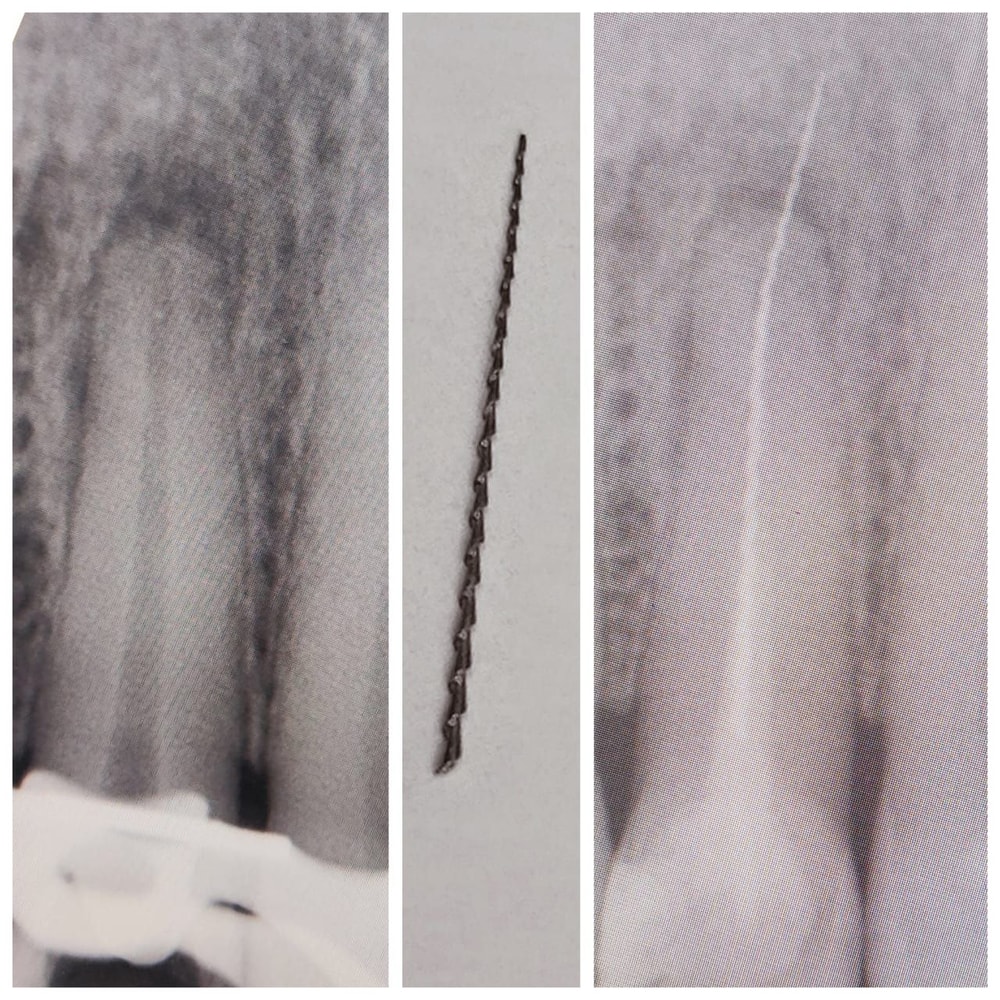

Марина 2 месяца Посоветуйте эндодонта в Москве. Сложный случай Есть такие проверенные стоматологи? Посмотрите еще 20 записей на эту тему Отменить Ответить Маргарита Сзао, бьюти стом, Каминская А.Ю. Делает невозможное 07.10.2025 Ответить Марина Маргарита, благодарю. Мне как раз такой специалист и нужен 08.10.2025 Ответить Валя Пашаева Диана Энверовна из Фэйс смайл центра. Она мне доставала обломок инструмента, территориально юзао 07.10.2025 Ответить Марина Валя, какого инструмента??? Мне полечить зуб под микроскопом нужно, а другой зуб спасти в полном смысле слова 08.10.2025 Ответить Валя Марина, вот так. и Диана Энверовна доставала мне его 08.10.2025 Ответить Электрическая двусторонняя сковорода Isottcom. Отзыв У кого какая напольная вешалка? Чаты Беременных Выберите чат: Январята-2026 Февралята-2026 Мартята-2026 Апрелята-2026 Майчата-2026 Июнята-2026 Июлята-2026 Августята-2026